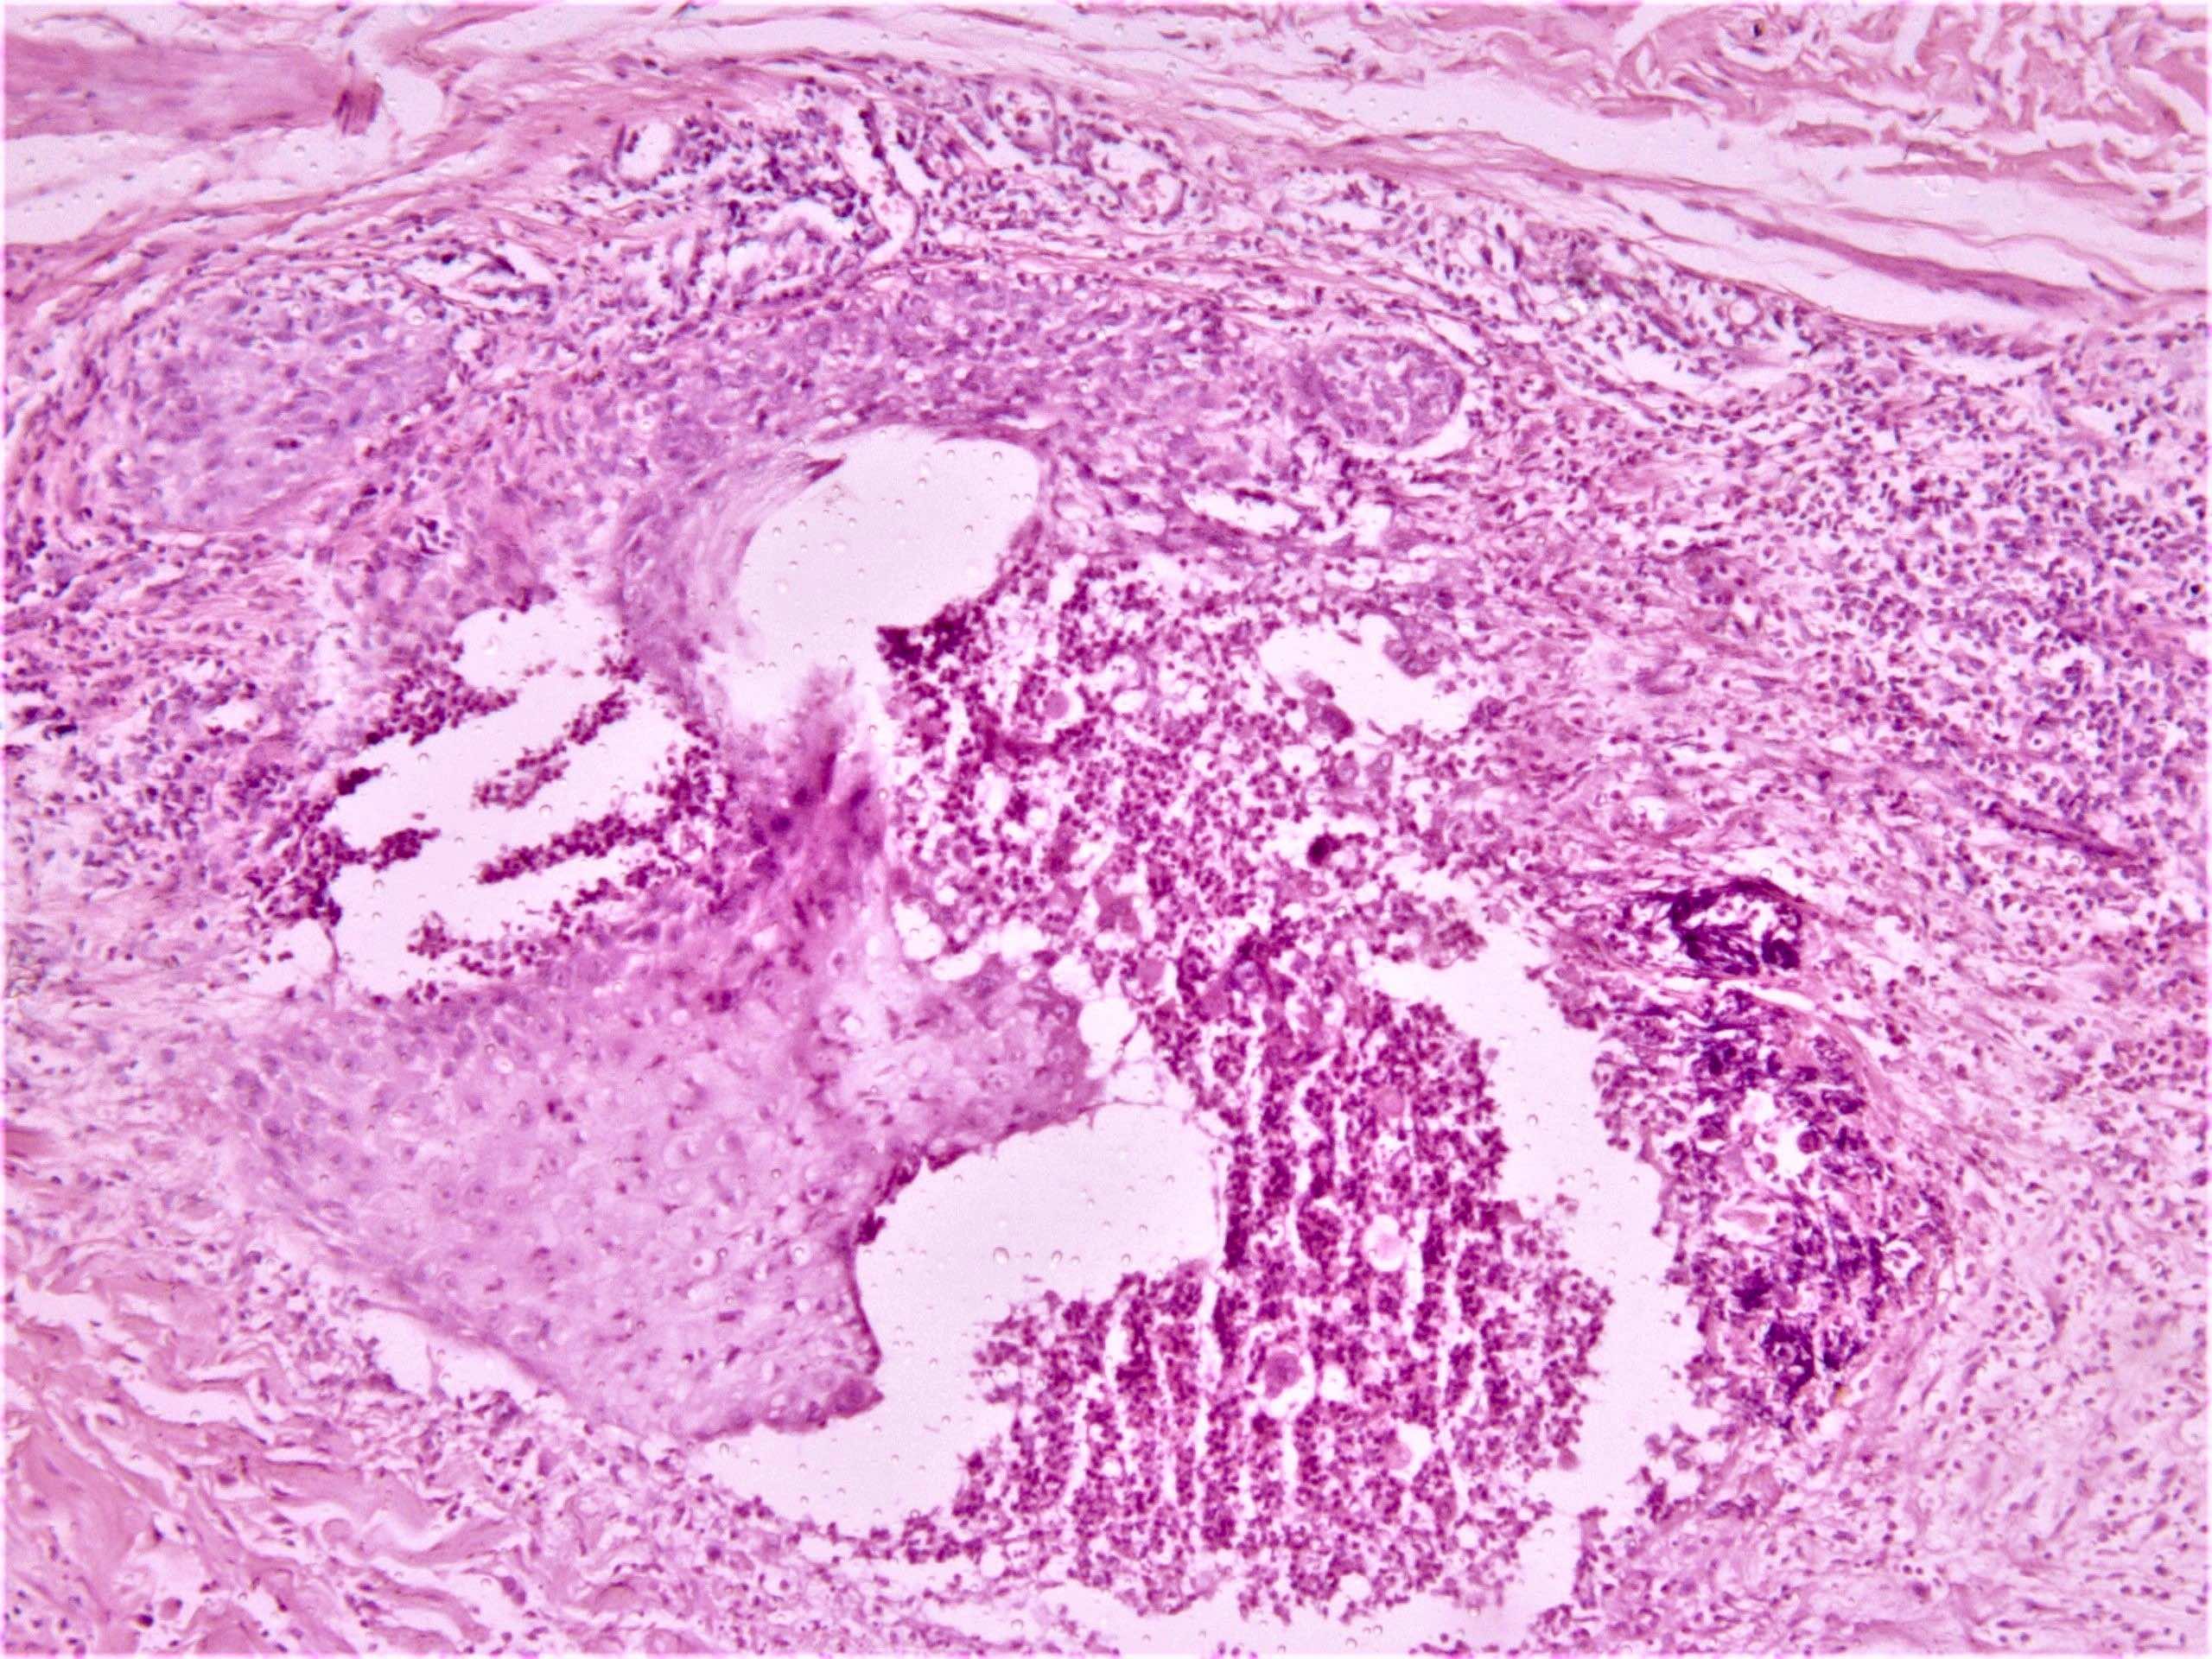

Microscopic (histologic) description

- Papulopustular lesions: spongiosis, basal keratinocyte vacuolization, intraepidermal pustules, suppurative folliculitis

- Thrombophlebitis: thrombi in vessel lumens, perivascular inflammatory infiltrate

- Leukocytoclastic vasculitis

- Reference: Patholog Res Int 2012;2012:209316

Microscopic (histologic) images